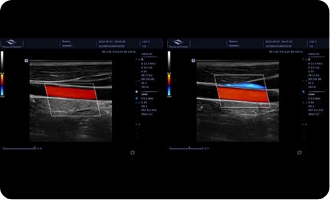

Auto Track-C

Szybkie ponowne lokalizowanie obszaru zainteresowania (ROI) na naczyniu krwionośnym za pomocą jednego przycisku. Zmniejsza obciążenie lekarza związanego z częstym dostosowywaniem pozycji i kąta ROI w zależności od różnych lokalizacji naczynia, poprawiając efektywność pracy.

Obrazy kliniczne